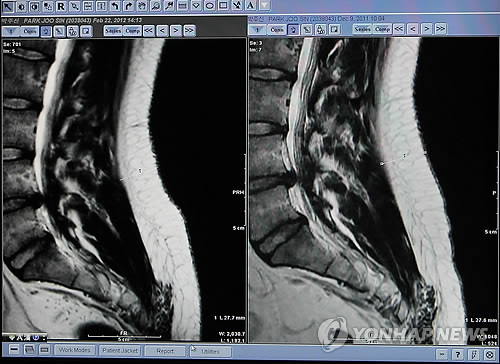

¹ÚÁÖ½ÅÀÇ MRI »çÁøÀÌ ¸Â´Ù´Â ¼Ò°ßÀÌ ³ª¿À°í

¹ÚÁÖ½ÅÀÌ ½ÇÁ¦ 4±ÞÆÇÁ¤À» ¹ÞÀ»Á¤µµ·Î µð½ºÅ©»óŰ¡ ¾ÈÁÁ´Ù´Â °ÍÀ» »ç½ÇÀ̶ó°í ¼ö¿ëÇÏ´Â ÀÔÀå¿¡¼­ ¹Ú¿ø¼øÀÇ ±ä½Ã°£ ¸ð¸£¼è ´ëÀÀ¿¡ ÀǽÉÀ» °¡Á®º¸´Â °Í, ±×¸®°í °ø°³°ËÁõÀ» Àü°ÝÀû ÀÏ»çõ¸®·Î ÁøÇà½ÃŲ°Í¿¡ ´ëÇØ ÀǽÉÀ» °¡Áø´Ù.

¾î¸¶¾î¸¶ÇÑ º¯È£»ç¸¦ »ç¼­ ¹Ì¸® °èȹµÈ ÀÛÀü¼öÇàÇϵí Àü·«ÀûÀ¸·Î °ø°³°ËÁõÀ» ÇØÄ¡¿ì´Â ±×°ÍÀÌ ¹ÚÁÖ½ÅÀÇ MRI»çÁø »ç½ÇÆÇÁ¤º¸´Ù ¿ÀÈ÷·Á ´õ Àǽɽº·´´Ù.

¹ÚÁÖ½ÅÀº ½ÇÁ¦ 4±ÞÆÇÁ¤¹ÞÀ» Á¤µµÀÇ »óȲÀÌ ¸Â´Âµ¥ Áö³ªÄ¡°Ô ´ëÀÀÇÏ´Â ¹Ú¿ø¼øÃøÀÌ ¿ÀÈ÷·Á ÀÌ»óÇß´Ù¶ó´Â »ý°¢ÀÌ µé±â¿¡ °Å²Ù·Î ¹ÚÁÖ½ÅÀÌ º´¿ªºñ¸® ¸ÂÁö ¾ÊÀ»±îÇÏ´Â Àǽɵµ µç´Ù.